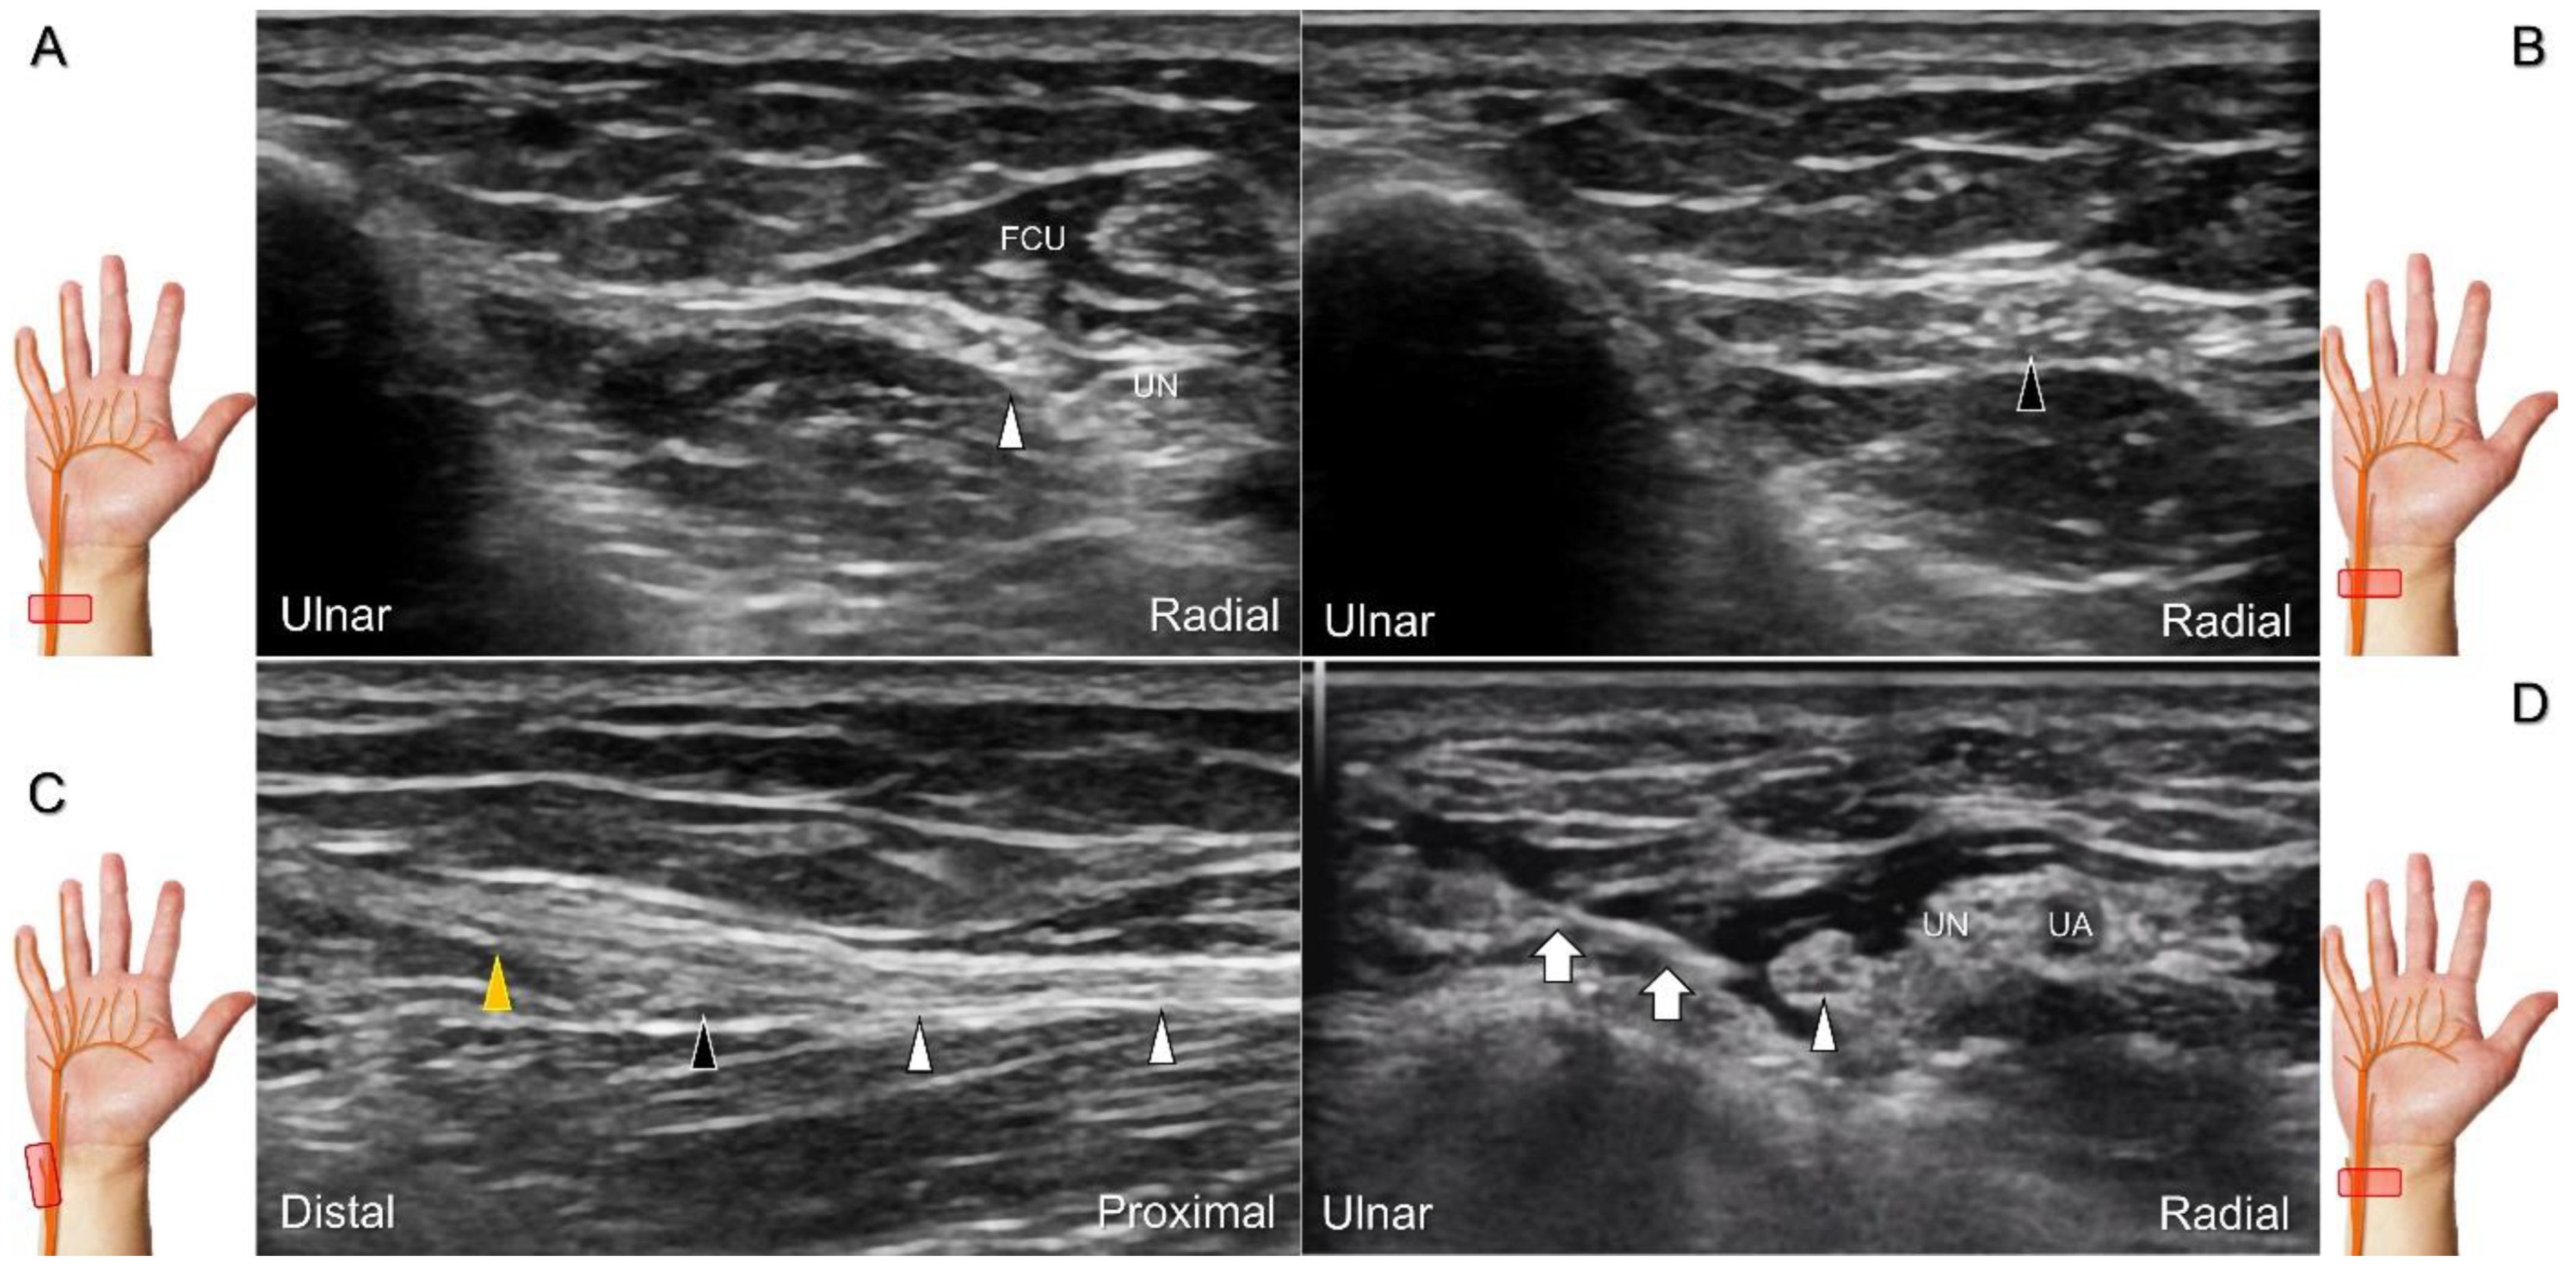

Scanning Technique

To locate the Guyon’s canal, the transducer is placed along the axial plane on the volar wrist with the forearm supinated. This will reveal the ulnar nerve and artery within the canal (Figure 13A). To investigate the nerve’s long axis, the transducer is rotated 90 degrees. By moving the transducer toward the finger, the superficial and deep branches can be seen. Between the pisiform and hamate, the superficial and deep branches (along with their accompanying vessels) can be visualized as separated by the fibrous arch of hypothenar muscles, respectively (Figure 13B) [39].

The superficial branch divides into two palmar digital nerves. They run superficially along the little finger and half of the ring finger. The deep branch, on the other hand, can be observed between the flexor digiti minimi brevis and opponens digiti minimi muscles before it penetrates the deep aspect of the palm (Figure 13C). By pivoting the transducer, the physician can display the long axis of the deep branch, extending all the way to the segment within the adductor pollicis muscle (Figure 13D).

Figure 13. Sonographic imaging (short-axis view) shows the ulnar nerve within the Guyon’s canal (A), separation of branches beside the pisohamate hiatus (B), deep branch of the ulnar nerve located between the hypothenar muscles distal to the hook of the hamate (C). Long-axis view (through pivoting the transducer) shows the segment of the deep branch within the adductor pollicis muscle (D). Arrowhead: ulnar nerve; white arrows: superficial branch of the ulnar nerve; black arrows: deep branch of the ulnar nerve; orange arrow: branch of the ulnar nerve to the abductor digiti minimi; *: pisohamate ligment MN: median nerve; UA: ulnar artery; P: pisiform; H: hook of hamate; A: artery; L: lumbrical muscle; FDM: flexor digiti minimi brevis muscle; Opp DM: opponens digiti minimi muscle; AbDM: abductor digiti minimi muscle; AdP: adductor pollicis muscle.